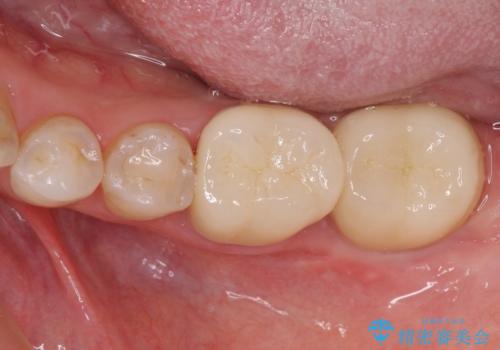

矯正治療後は、奥歯の虫歯や銀歯を補綴・修復治療することとしました。

上顎歯列を下顎に対して4mmほど移動させる必要があったため、治療は長期化することが予想されましたが、患者様にはこちらの期待以上にゴムかけなどに協力いただき、補綴治療も含めて2年強で終えることができました。